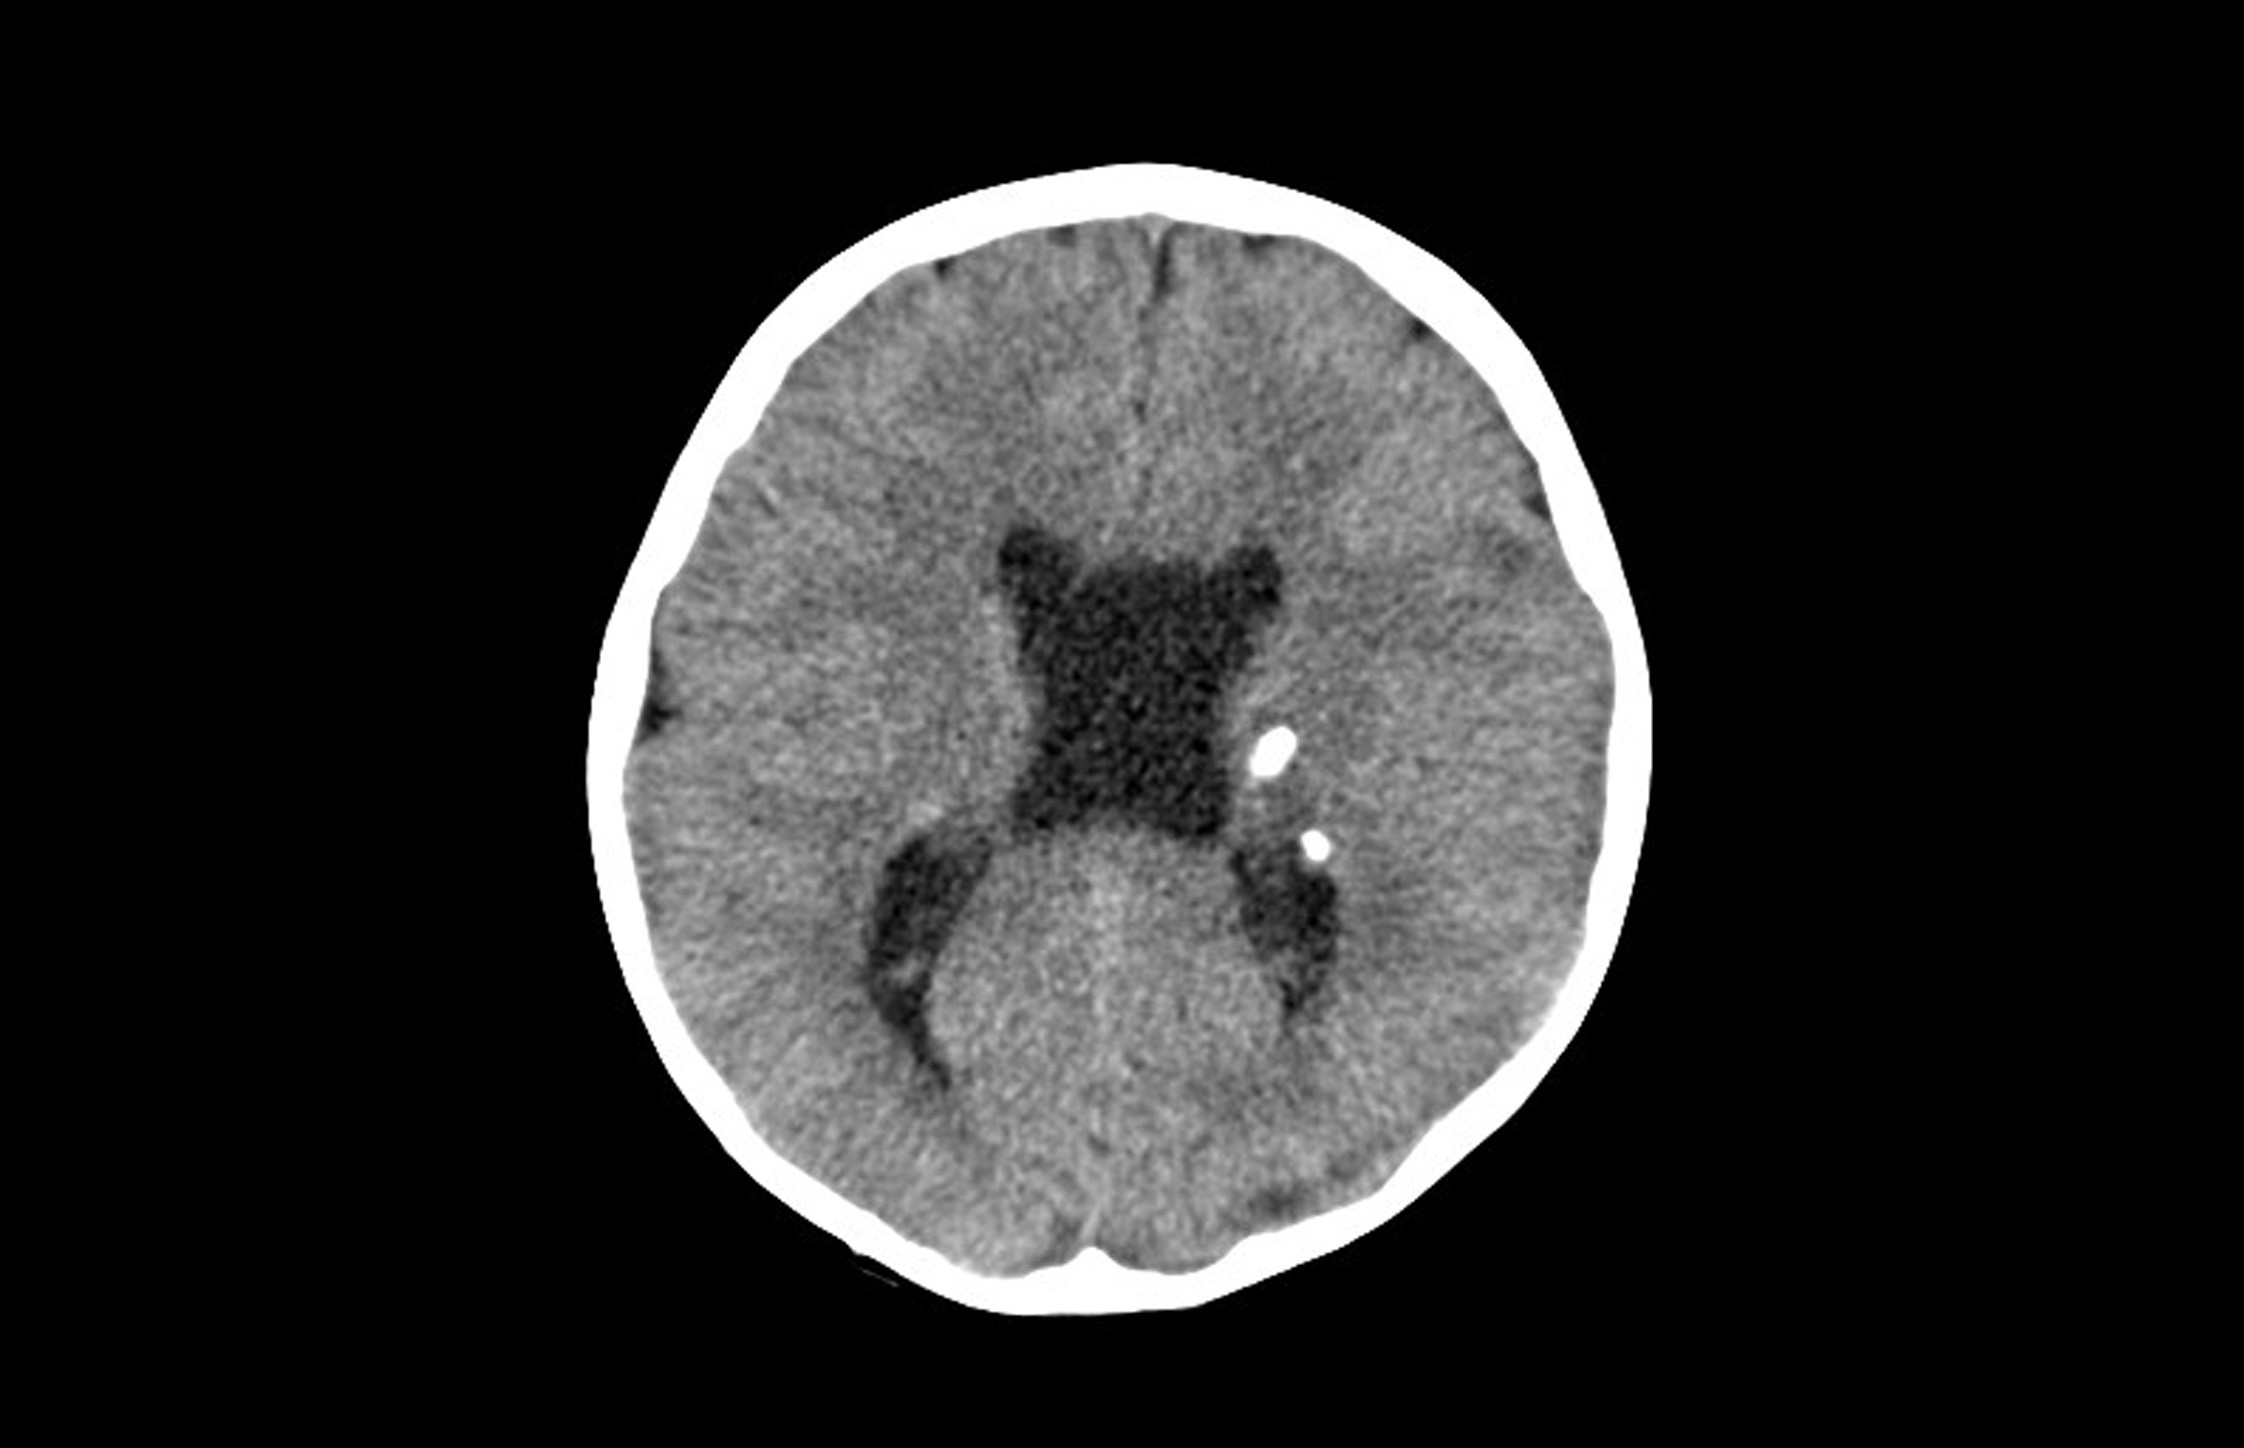

En Urgencias se realizan un análisis sanguíneo y de tóxicos en orina, con resultados normales. Se solicita una tomografía computarizada (TC) craneal (Fig. 1) en la que se identifican lesiones parenquimatosas, la mayoría calcificadas, con distribución periventricular.

Figura 1. TC craneal (corte axial): lesiones parenquimatosas calcificadas periventriculares

• Tumores cerebrales: la lesión cerebral característica es el tuber cortical (hamartomas de la sustancia gris localizados en las circunvoluciones de los hemisferios cerebrales y en la región subependimaria). Pueden calcificarse y protruir en la luz del ventrículo, lo que produce unas imágenes características en “goteo de vela”, u obstruir el agujero de Monro y provocar hipertensión intracraneal. Raramente evolucionan a astrocitomas malignos. El SEGA es característico del complejo esclerosis tuberosa. Todas estas lesiones pueden identificarse mediante TC craneal, especialmente si están calcificadas, siendo la RM más sensible7.